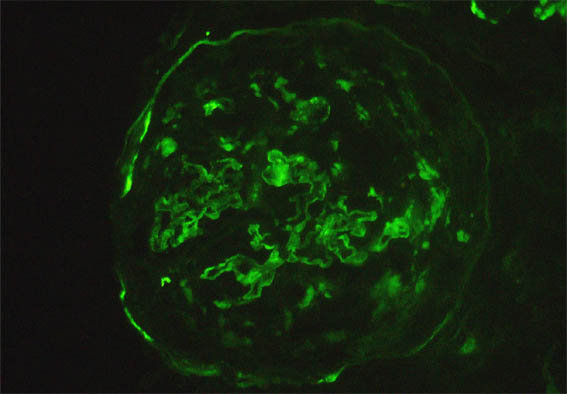

Figura 11. Inmunofluorescencia directa para C3, X400.